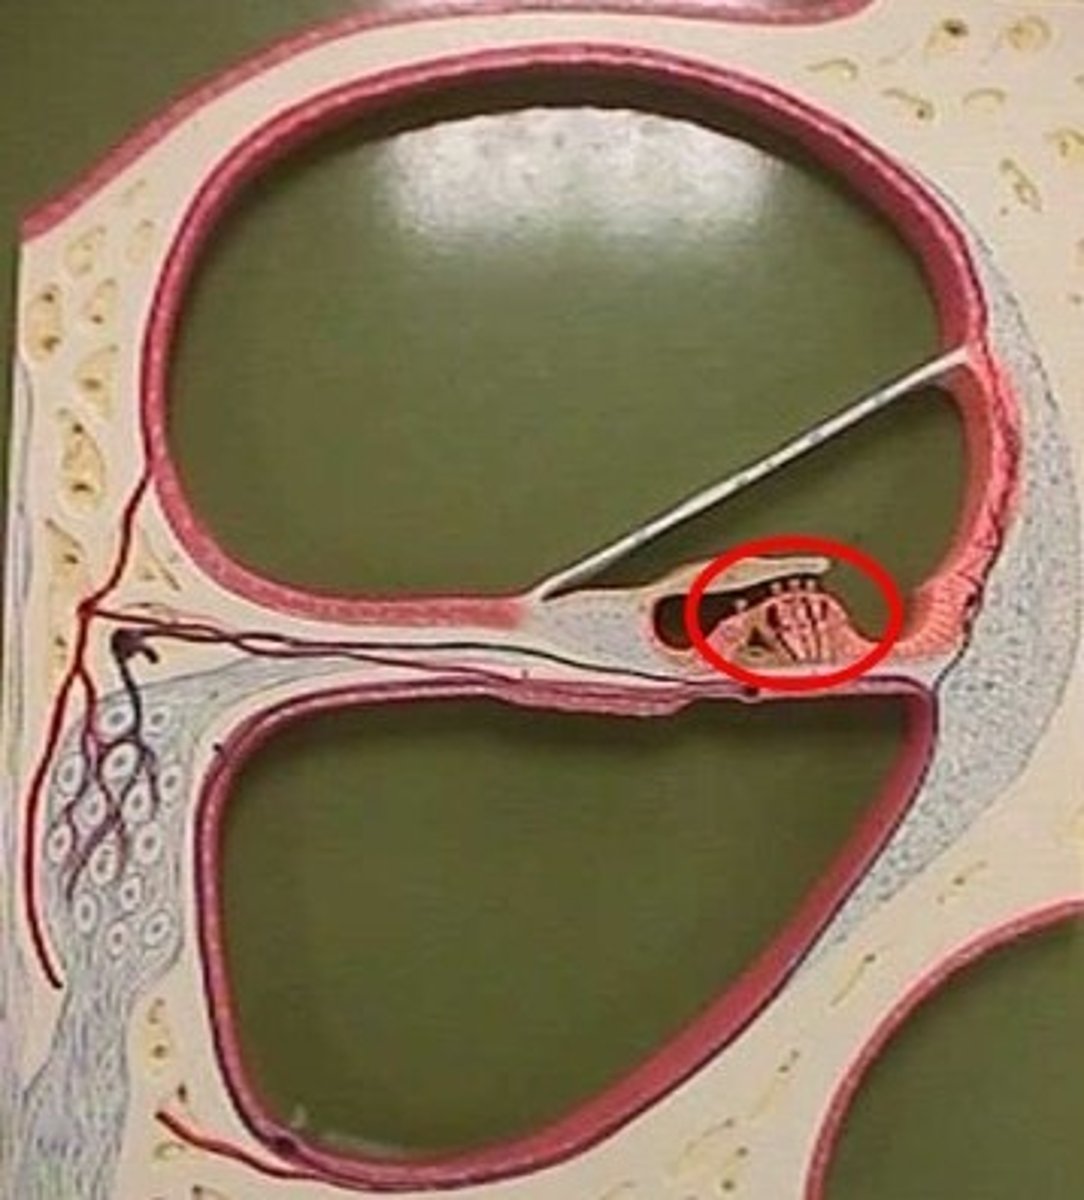

anterior cavity (of eye)

iris

B

optic disk (blind spot)

choroid

L

ciliary body

B

ciliary process

conjunctiva

cornea

D

fovea centralis

suspensory ligaments

C

vitreous humor

lens

H

macula lutea

nasolacrimal duct

lacrimal gland

posterior cavity (of eye)

pupil

F

retina

M

sclera

optic nerve